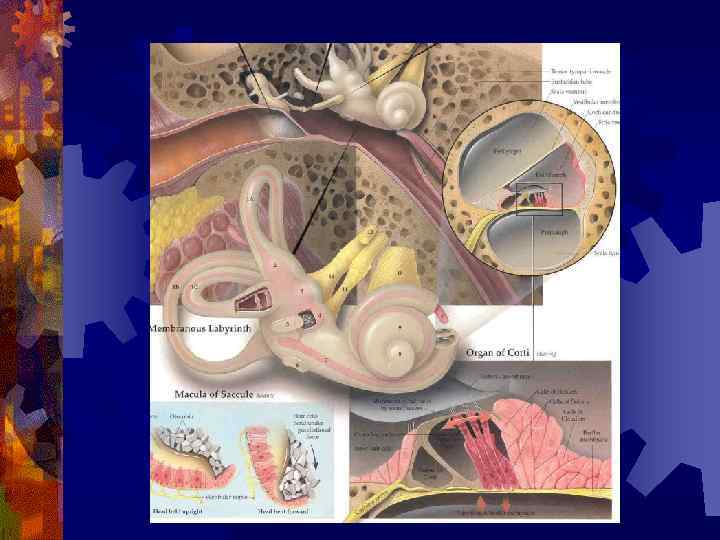

Анатомия

Физиология слуха